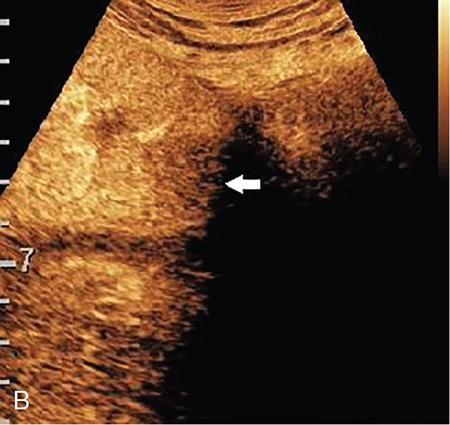

Drushi Patel CONTRAST-ENHANCED ULTRASOUND IN ADULT GENITOURINARY IMAGING Mridula Muthe Ultrasound is the initial screening examination for the evaluation of the renal morphology and suspected renal lesions due to its multiple advantages such as easy accessibility, bedside assessment, affordability and lack of radiation. Vascularity of the kidney and renal lesions can be studied with the use of colour Doppler ultrasound however, it provides information only about the macrovasculature. With the use of microbubble ultrasound contrast agents (UCAs) macro as well as the microvasculature can be studied. Contrast-enhanced ultrasonography (CEUS) is also more sensitive than Doppler ultrasound as it is not affected by blood velocity and angle of insonation of the ultrasound beam. In urology, the established applications of CEUS in adults include characterization of cystic lesions and differentiation between pseudotumours and solid lesions. Box 10.23.1.1 provides a list of European Federation of Societies for Ultrasound in Medicine and Biology (EFSUMB) recommended indications of CEUS in renal evaluation. EUROPEAN FEDERATION OF SOCIETIES FOR ULTRASOUND IN MEDICINE AND BIOLOGY (EFSUMB) RECOMMENDED INDICATIONS FOR USE OF UCA IN RENAL EVALUATION Renal ischaemia. Evaluation of solid renal lesions. Differentiation between solid renal lesions and pseudotumours. Characterization of complex cystic masses. Characterisation of indeterminate renal masses. Renal infections. Follow-up of nonsurgical complex masses. To improve lesion visualization in patients undergoing renal tumour ablation under US guidance and to detect residual tumour either immediately or after ablation. Isolated blunt moderate-energy renal trauma. Follow-up of trauma patients managed conservatively. Characterization of thrombus in renal vein and inferior vena cava. In patients with contraindications for CT- and MRI-based contrast media. Evaluation of lesions in transplant kidneys. Evaluation of ischaemia and vascular complications in transplant kidneys. Tumour response assessment to biologic therapy. Intracavitary CEUS for guiding percutaneous nephrostomy. Source: P.S. Sidhu, V. Cantisani, C.F. Dietrich, O.H. Gilja, A. Saftoiu, E. Bartels, et al., The EFSUMB guidelines and recommendations for the clinical practice of contrast-enhanced ultrasound (CEUS) in non-hepatic applications: update 2017 (long version). Ultraschall in der Medizin-Eur. J. Ultrasound 39 (02) (2018) e2–e44. CEUS involves the intravenous injection of UCAs consisting of gas microbubbles. These UCAs remain purely in the intravascular compartment as they are small enough to avoid filtration by the lungs and too large to enter the interstitial compartment. UCAs cause marked amplification of signals from the flowing blood, thus providing information about the microvasculature and parenchymal perfusion. Sonovue is a second-generation UCA and is the only UCA available in India. It consists of sulphur hexafluoride gas which is exhaled by the lungs and is surrounded by phospholipid monolayer which is metabolised by the liver, making it safe for patients with renal insufficiency. For renal evaluation, a dose of 1–1.5 mL of Sonovue is administered as a bolus dose followed by a 10 mL saline flush. CEUS is performed on machines with contrast-specific software’s using a low mechanical index (MI) technique. The use of a dual image display is beneficial for the evaluation of small lesions. A conventional B-mode ultrasound is first performed to acquire measurements, assess morphology and to detect focal lesions along with Doppler ultrasound to assess vasculature. However, due to limitations in the assessment of focal lesions, microvasculature, complex cysts, poor contrast between the lesion and cortex or medulla, it is preferable to perform a CEUS study for additional characterization. The enhancement pattern of the kidney is different than that of the liver due to the dual blood supply of the liver as opposed to afferent arterial supply and efferent venous drainage of the kidney. After an intravenous bolus of UCA, kidneys show intense enhancement. Contrast is first seen in the main renal artery, followed by its branches. CEUS has only two enhancement phases, that is cortical phase which lasts for 15–30 seconds and a parenchymal phase (enhancement of both cortex and medulla) for 25 seconds–4 minutes after UCA administration. The renal cortex enhances first, followed by the outer medulla which is followed by gradual enhancement of the pyramids (Fig. 10.23.1.1). During the washout phase first, there is a reduction in the medullary enhancement followed by a slower washout of the cortex. As kidneys don’t excrete UCAs, there is no opacification of the pelvicalyceal system. UCAs can act as a problem-solving tool in patients with renal failure as they are not nephrotoxic. Due to its excellent ability to depict renal vascularization, it can be used for detecting perfusion abnormalities. CEUS is useful for detecting vascular causes of renal function deterioration. Renal infarcts appear as wedge-shaped nonenhancing areas in all phases. Renal infarcts show a focal complete lack of parenchymal enhancement on CEUS whereas ischaemic areas show reduced enhancement. CEUS can confidently differentiate infarction from cortical necrosis by the demonstration of preserved hilar vascularity in the latter. Renal pseudotumours such as foetal lobulations, dromedary hump, parenchymal hypertrophy due to renal scarring and column of Bertini can be accurately differentiated from true tumours using CEUS. Pseudotumours show similar enhancement to the adjacent parenchyma and appear isoechoic on all phases while true tumours show different enhancement pattern on at least one phase (Fig. 10.23.1.2). True tumours will cause mass effect and distort the normal vascular architecture of the renal parenchyma whereas in pseudotumours the vascular architecture is preserved. In addition, the identification of medullary pyramids within the mass points towards it being a pseudotumour rather than a true mass. Cysts can be categorized according to the Bosniak classification using CEUS. Due to its superior spatial and temporal resolution, CEUS is considered superior to CT for detecting additional septations, wall or septal thickening and solid components (Figs 10.23.1.3–10.23.1.5). CEUS allows for real-time imaging of blood flow within the septae, wall or nodules within the cysts which may not be seen on CT or MR imaging. The sensitivity of CEUS is comparable to CT for the classification of renal cystic lesions as benign or malignant however, it is not as useful for staging. The follow-up of inoperable complex cystic lesions is better performed with CEUS rather than CT due to the absence of ionizing radiation. Complex cysts or masses with calcifications are not suitable for evaluation with CEUS. CEUS allows a detailed evaluation of the circulation in mass lesions as it demonstrates the macro as well as microvascular enhancement patterns. CEUS has more sensitivity than CT for detecting blood flow in hypovascular lesions. It can also be used to distinguish between complex cysts and solid lesions which remain equivocal on CT and ultrasound (B-mode and colour Doppler). CEUS is sensitive in identifying cystic areas, necrosis, debris and haemorrhage in small tumours that may be difficult to visualize on CECT and MR. Isoechoic lesions on conventional ultrasound are better characterized by CEUS (Fig. 10.23.1.6). Hyperdense renal lesions on noncontrast CT (NCCT) with HU values between 20 and 70 are better evaluated by CEUS which can classify these lesions as solid or cystic. CEUS can suggest the histological subtype of tumours. Clear cell carcinomas show heterogeneous hyperenhancement in the cortical phase and rapid washout along with a peripheral enhancing rim or pseudocapsule seen during the parenchymal phase. Papillary carcinoma shows progressive heterogeneous enhancement during the cortical phase and displays hypoenhancement as compared to the cortex on all phases. Malignant renal vein thrombus will show enhancement as compared to bland thrombus on CEUS. Tumours that are smaller than 3 cm commonly show homogeneous enhancement, regardless of their histologic subtype. Differentiation between angiomyolipoma, renal cell carcinoma and oncocytoma is not always possible. Although, CEUS has excellent sensitivity for the detection of malignancy, it has a higher false-positive rate as compared to CECT. Hence, combined use of CEUS for its high sensitivity and CECT for its high specificity may be performed for an accurate diagnosis. CEUS is effective in patients with complicated pyelonephritis, for identifying inflammatory parenchymal involvement, characterized by round or wedge-shaped hypovascular parenchymal areas, most conspicuous during the late parenchymal enhancement phase. An abscess is seen as a nonenhancing area, with or without peripheral or septal enhancement. CEUS can also be used for the follow-up of renal abscesses. All the aforementioned indications of CEUS in native kidneys also apply to renal transplants. Infarction, vascular complications such as arterial and venous thrombosis can be detected. Quantitative CEUS for assessment of graft dysfunction is a subject of active research. CEUS can be used as an alternative to CT especially in children with isolated blunt moderate energy injuries who are hemodynamically stable. It can also be used in the follow-up of conservatively managed trauma patients and in renal impairment. During Focused Assessment with Sonography for Trauma (FAST), the examination should begin with the kidneys as they have a fleeting enhancement. The kidneys are studied in the arterial phase with two separate doses administered for either kidney during FAST. On CEUS, lacerations, hematomas, and infarcts are seen as nonenhancing areas on late-phase images whereas contusions may show faint enhancement. Pseudoaneurysms and active bleeding are diagnosed on the arterial phase. Crucial complications such as devascularized parenchyma and acute cortical necrosis can also be diagnosed on CEUS. Pelvicalyceal system injury cannot be detected by CEUS as UCAs are not excreted by the kidneys. CEUS can be performed in conjunction with percutaneous ablation therapies. Preablation evaluation with CEUS is essential to assess lesion vascularity and to compare pre and postprocedure tumour viability. Also, the identification of a pseudocapsule predicts improved ablation efficacy. CEUS has demonstrated high sensitivity, specificity and accuracy for the early detection of residual unablated tumour. Dynamic contrast-enhanced ultrasound is a useful tool for early identification of responders and nonresponders, enabling tailoring of the treatment regimen. It is performed by two methods – Bolus injection of a UCA with time-intensity curve analysis (commonly used) and intravenous injection of UCA with disruption–replenishment analysis. In patients with chronic kidney disease, the contrast enhancement is less intense and fades earlier as compared to a normal kidney. CEUS aids in characterizing renal lesions in patients with renal failure. Characterization of lesions with indeterminate appearances in patients with renal dysfunction, on conventional US prevents unnecessary further evaluation with contrast-enhanced CT or MRI and further deterioration of the renal function as well as unwarranted investigations. CEUS nephrostomogram can be performed after percutaneous nephrostomography to confirm the correct positioning of its tip, detect the site of obstruction and to diagnose complications. UCAs can be safely administered in patients with minimal risk. They can be safely administered in patients with renal insufficiency as they are not excreted by the kidneys. Prior laboratory tests are not indicated as they are not nephrotoxic and don’t interact with thyroid function. Most adverse effects are mild such as nausea, headache, chest discomfort, chest pain and resolve spontaneously. The contraindications include known hypersensitivity, patients with right-to-left shunts, severe pulmonary arterial hypertension (pulmonary arterial pressure >90 mm Hg), uncontrolled systemic hypertension, and respiratory distress. The rate of anaphylactic reactions is significantly lower than iodinated contrast media and comparable to gadolinium-based contrast agents. Caution should be exercised in patients with severe acute coronary disease and in patients with unstable angina. CEUS is a rapidly evolving technique, can be conveniently performed as an extension of conventional ultrasound and acts as a valuable tool in the characterization of indeterminate renal lesions, especially when the lesion is small. The advantages of CEUS include quick assessment, real-time imaging, high contrast resolution, excellent safety profile, lack of ionizing radiation, great repeatability, and most importantly, ideal for contrast evaluation in patients with deranged renal function. DUAL-ENERGY AND SPECTRAL IMAGING IN GENITOURINARY SYSTEM Aditi Chaitanya Gujarathi-Saraf Dual-energy CT (DECT) also known as ‘spectral imaging’, was first conceptualized in the 1970s. However, the clinical applications of DECT have recently emerged as owing to improvements in postprocessing techniques. The development of a single-detector, single-source DECT (ssDECT) with the capability for rapid alternation between two peak voltage settings (‘fast switching’) and a dual-detector, dual-source DECT (dsDECT) system in last few years have made possible various applications in solving clinical problems. In DECT, the simultaneous use of two different X-ray beam energy settings (80 and 140 kVp) allows the differentiation of materials on the basis of their attenuation characteristics (material density). There are two major applications of DECT in genitourinary system. First being characterization of renal calculi to differentiate those containing uric acid (UA) from those which do not. The other application is to characterize small renal masses which include differentiating complex cysts from renal tumours, detection of solid growth in PCKD patients and detection of residual tumour after thermal ablation of a renal neoplasm. The principle of DECT imaging is based on the differential absorption of X-ray energy at variable kVp settings. In DECT, two energy levels (typically 80 and 140 kVp) are used to acquire images that can be processed to generate additional datasets. Thus, a tissue or any material in the body shows different degrees of attenuation when scanned at different X-ray energies. Conventional CT numbers (attenuation measurements in Hounsfield units) are related to the linear attenuation coefficient of a particular material. The unique linear attenuation coefficients obtained by imaging at two different energies can be used to discriminate between different materials (e.g. fat, calcium, iodine and water). The characterization of material on DECT depends on their CT number ratio (CTR) also called dual-energy ratio. DE RATIO = CT number of a given material in the low-energy image CT number of the same material in the high-energy image DECT and spectral CT can be performed by three techniques (Fig. 10.23.2.1): Two sets of material-specific images are created to detect the presence or absence of a material. The two basic materials selected should have significant difference in mass attenuation coefficients and atomic number. The two commonly selected pairs are: Iodine-specific images are most commonly used in the clinical practice. When iodine is paired with water, two separate image data sets are generated. On water density image, the voxels that show change in attenuation due to presence of iodine are removed. These are instead represented on iodine density images. Thus, virtual unenhanced images are generated which resemble the conventional unenhanced images. Renal calculus disease is a common disease affecting approximately 10%–14% of population in India commonly affecting 31–45-year-old patients. Accurate diagnosis of composition of renal calculi is crucial as the frequency of prevalence and recurrence rate of renal calculi is high in most states of India. The obstructing calculi can lead to obstructive uropathy, pyelonephritis, urinary sepsis with nearly 50% of the patients being affected by renal failure. There are multiple compositions of renal calculi, most common being calcium oxalate (70%), calcium phosphate (20%), uric acid (8%) and cystine (2%). In general, UA calculi have lower attenuation values than nonuric acid calculi (i.e. struvite, cystine and calcium) on conventional CT. However, it may be difficult to distinguish between the two due to overlap in attenuation values. Here DECT becomes a problem-solving tool as it uses the two-material differentiation approach. Thus, in addition to size and location, DECT provides information about the composition of calculi to the urologist. DECT has high sensitivity of 88%–100% and high accuracy of 93%–100% to differentiate UA calculi from nonuric acid UA calculi. This is of utmost clinical importance as UA calculi can be treated medically whereas non-UA calculi require invasive methods of treatment such as extracorporeal shockwave lithotripsy (ESWL) or percutaneous nephrolithotripsy (PCNL). In clinical practice, NCCT scan of KUB region is performed at 80 and 140 kVp to generate two image datasets and obtain the DE ratio. A cut-off value of DE ratio of 1.2 is used to differentiate UA calculi from non-UA calculi (Fig. 10.23.2.2). Following flow chart shows differentiation of renal calculi based on DE ratio.